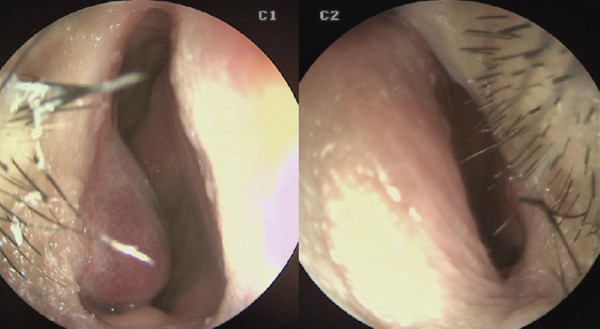

![]()

비중격 및 비밸브 교정 전. 연골부 일부가 이전 양악수술로 인해 소실된

모습이다. 비중격이 전체적으로 좌측 만곡되어 C-shape deviation이

확인되었다.

수술장 소견상 비중격 연골부 일부가 이전 양악수술로 인해 소실된 모습이 보였고, 전체적으로 좌측으로 만곡된 C-shape deviation이 확인되었다. 또 한 비익연골의 내전과 비중격 미단부의 변형으로 인해 좌측 비밸브 부위가 좁아져 있음이

관찰되었다.